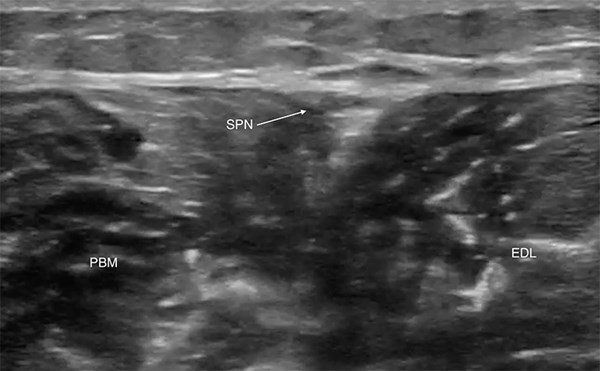

Nerves can exhibit strong anisotropy

- Anisotropy refers to the changes in echogenicity of a structure as the angle of insonation is changed.

- Care must be taken to adjust the angle of insonation to ensure optimal nerve visualization.

- Tendons, ligaments and muscle also exhibit anisotropy.